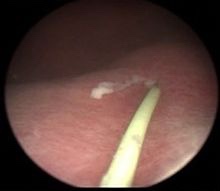

Chyluria flow during cystoscopy and ureteral catheterization.

Once the lymph channels are blocked, one may open into the kidney hilum or ureter or sometimes into the bladder and chyle can leak into the urinary tract resulting in milky white urine. Blood sometimes mixes with the urine resulting in haemato-chyluria.